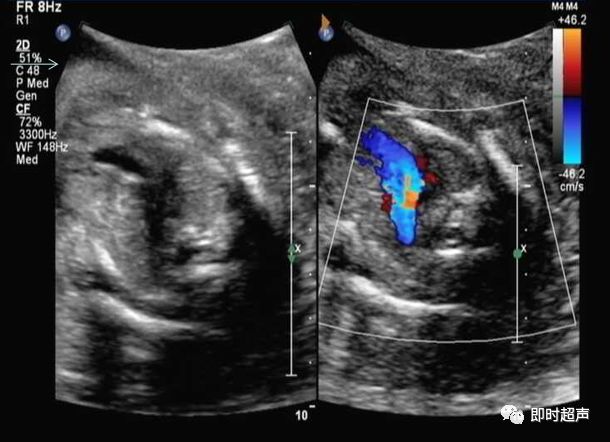

肺动脉血流反向

右心发育不良综合症(三尖瓣或肺动脉瓣闭锁或重度狭窄)

五、血流方向的异常

主动脉弓或肺动脉血流方向相反是导管依赖型心脏畸形的典型表现

动脉导管依赖型心脏畸形,是指出生时新生儿的存活依赖于动脉导管的开放,如果动脉导管闭锁了,那么体循环和肺循环之间的沟通也就终止了,新生儿就会迅速死亡的一类心脏畸形。